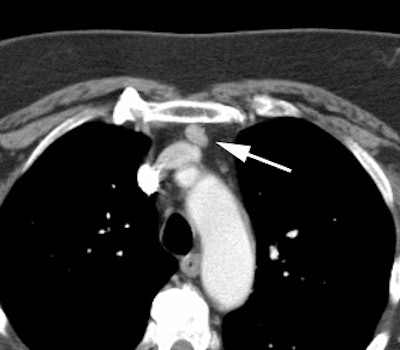

Ectopic parathyroid adenoma: The patient in the case below presented with hyperparathyroidism. A dual phase Tc-MIBI examination revealed a persistent focus of tracer accumulation in the chest (black arrows) on both early and delayed imaging. A SPECT exam was performed to better localize the abnormality which can be seen in the anterior mediastinum (click SPECT images to view cine). CT scan confirmed a soft tissue nodule in the anterior mediastinum (white arrows). At surgery, the patient was found to have an ectopic parathyroid adenoma. |